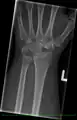

- Left hand x-ray with Kienbock's Disease showing 4 mm negative ulnar variance and Kienbock's Disease Stage IIIB

- X-ray showing stage IIIB on right wrist, with ulnar impingement.